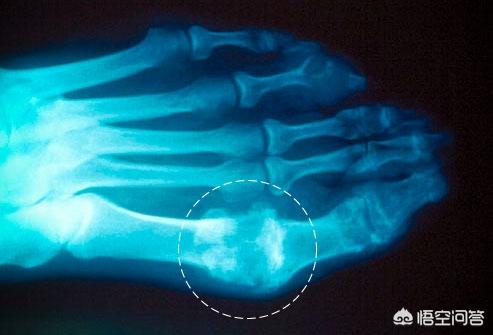

但是如果人体对于尿酸的代谢出现问题,导致尿酸在血液中累积,就会导致尿酸的逐步升高,一步步的走向“高尿酸”。当尿酸值超出正常范围,血液中的尿酸就“太”多了,为什么尿酸多了会有危害,还是跟尿酸的性质有关,尿酸是一种微溶于水的核酸类化学物质,如果它在血液中出现了过饱和,就会析出单尿酸盐的结晶,这些细小的结晶随着血液游走,也可能会出现沉积,如果沉积于关节部位,在某些诱因的情况下,导致关节部位出现剧烈疼痛、红肿,灼热等不适感觉,就是“痛风”。

痛风是单钠尿酸盐结晶沉积所致的晶体相关性关节病,与高尿酸血症直接相关,但并不是所有的高尿酸血症都会发生痛风。痛风发生的前提是血尿酸水平升高超过饱和度而出现结晶析出(就如同向水里加盐一样,当超过饱和度食盐就不能溶解而会析出),并沉积在关节等组织处引起炎症反应,就诱发了痛风的发生。 我们正常饮食下非同日两次空腹八小时以上测得血尿酸水平升高超过420umol/L,即可诊断高尿酸血症。约5~12%的高尿酸血症患者最终会出现痛风,所以并不是所有的高尿酸血症患者都会出现痛风,但我们大家还是要重视高尿酸血症。痛风并不可怕,我们日常生活中要注意改善生活方式,并配合规律服用降尿酸药物,以达到控制血尿酸水平,避免尿酸盐结晶析出,减少痛风发作风险的目的。高尿酸血症患者启动降尿酸药物治疗的时机主要有以下几项:①无症状高尿酸血症患者,当血尿酸水平超过540umol/L,建议使用降尿酸药物,控制血尿酸水平低于420umol/L为宜;②有高血压、糖尿病、高脂血症、冠心病、脑卒中等基础疾病时,当血尿酸水平超过480umol/L,建议使用降尿酸药物,控制血尿酸水平低于420umol/L为宜;③出现痛风时,只要血尿酸升高就应使用降尿酸药物,控制血尿酸水平低于360umol/L为宜,如有痛风石或慢性痛风性关节炎频繁发作者,应控制在300umol/L以下。 降尿酸药物主要有抑制尿酸生成的别嘌醇、非布司他和促进尿酸排泄的苯溴马隆,具体药物选择应在医生指导下进行,药物使用过程中要注意监测病情变化,并注意定期复查。同时还要注意限制高嘌呤食物的摄入、戒烟限酒、控制体重、注意保暖、适当运动、多饮水、规律作息和保持良好的心态。